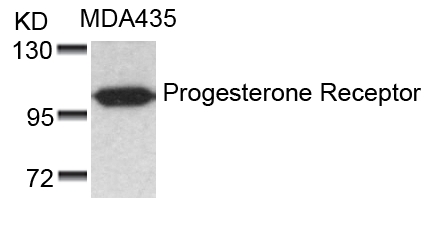

分类: 科研抗体货号: P41297别名: NR3C3; PGR; PRGR应用: WB,IF反应种属: Human